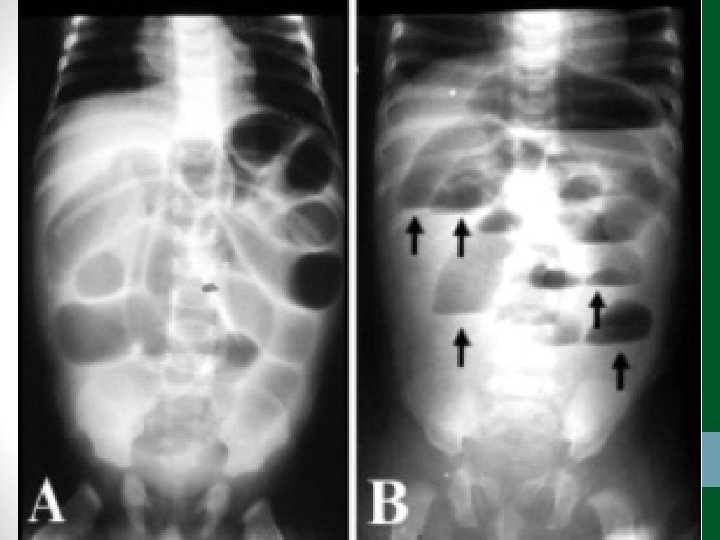

Exames de Imagem • Abdome Agudo Obstrutivo: • Radiografia simples de abdome: decúbito, ortostase e cúpulas diafragmáticas • USG abdome não ajuda! • TC Abdome com contraste VO e EV se não houver resolução em 48 h de tratamento clínico ou de acordo com suspeita clínica

Abdome Agudo Vascular • 50 a 70% de mortalidade • Causa relevante de óbito em pacientes internados em UTI • Diagnóstico e tratamento precoces (até 6 h do início da dor) aumentam a sobrevida • Requer alto índice de suspeição, pois os sintomas são inespecíficos no início do quadro • Pode ser confundido com quadro de obstrução intestinal

Abdome Agudo Vascular • Etilogia: • Isquemia arterial oclusiva • Embolia (50%) • Trombose (20%) • Isquemia arterial não-oclusiva (25%) • Trombose venosa (5%)